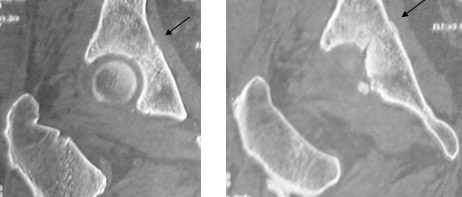

Les fractures fémorales atypiques : quoi de neuf ?

Des rapports récents suggèrent une relation entre un sous-groupe de fractures sous-trochantériennes et diaphysaires du fémur (fractures atypiques) et le traitement par bisphosphonates (BP). Une étude récente, faite à partir des grands essais (FIT, FLEX, HORIZON) évaluant des agents ostéoporotiques (Black et al, N Engl J Med 2010), ne retrouve pas de relation significative.

Le risque de fractures sous-trochantériennes ou diaphysaires associé à l’utilisation prolongée de bisphosphonate apparaît très faible, même chez les femmes ayant reçu jusqu’à 10 ans de traitement, comparativement aux fractures prévenues par ces traitements. Plusieurs communications ont abordé ce problème.

Attention aux écarts de conduite

Dr Jacques Fechtenbaum Hôpital Cochin - Paris

Vous suivez Mme D., 60 ans, depuis 3 ans pour une ostéoporose avec un T score à -3 DS au rachis lombaire et -2,7 DS au total col fémoral, au début de votre traitement par bisphosphonate.

Elle vient vous consulter pour une douleur de la « hanche » depuis 3 jours, date à laquelle elle a glissé lors d’une séance de gymnastique et fait un grand écart.

Elle présente une douleur de la face postérieure de la fesse gauche et une douleur à l’appui.

Les radiographies standard sont normales.